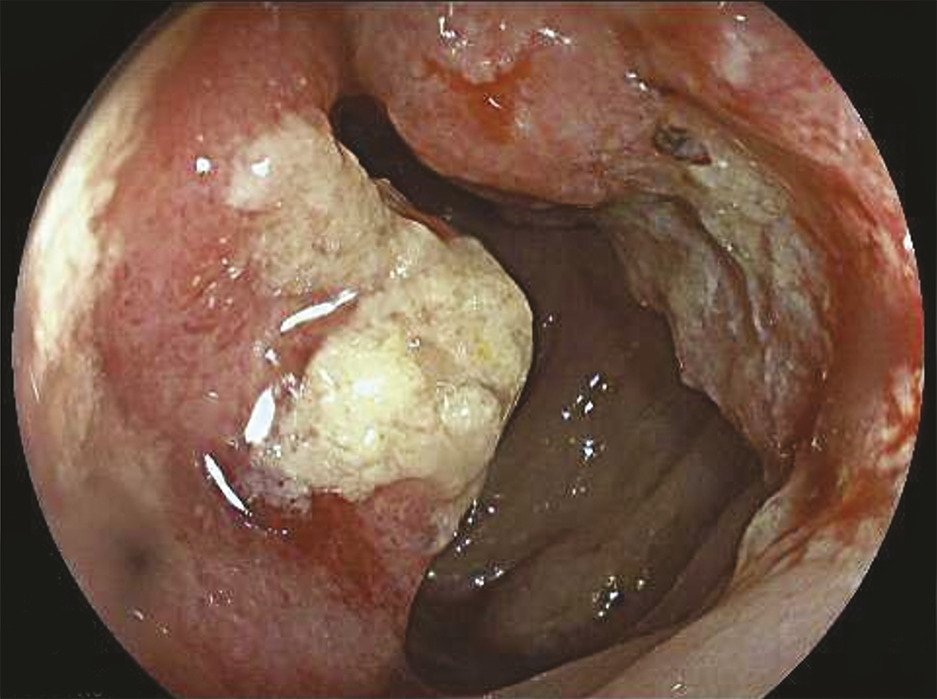

La coloscopie, sous anesthésie générale, est l’examen de première intention dans la plupart des cas de rectorragies. Si elle met en évidence une tumeur rectale, elle peut être complétée immédiatement ou dans un second temps par une rectoscopie rigide, permettant d’évaluer plus précisément la distance entre le pôle inférieur de la tumeur et la marge anale (mesure la plus reproductible) et/ou le pôle supérieur du sphincter. L’examen endoscopique permet également de décrire la lésion rectale (taille, aspect macroscopique, circonférence d’implantation) et de recueillir de multiples biopsies, indispensables au diagnostic (fig. 1 et 2 ).

– la présence ou non d’arguments en faveur d’une histologie mucineuse, de plus mauvais pronostic (tumeur en hypersignal T2)4 [fig. 4 ] ;

– la présence ou non d’arguments en faveur d’une histologie mucineuse, de plus mauvais pronostic (tumeur en hypersignal T2)4 [